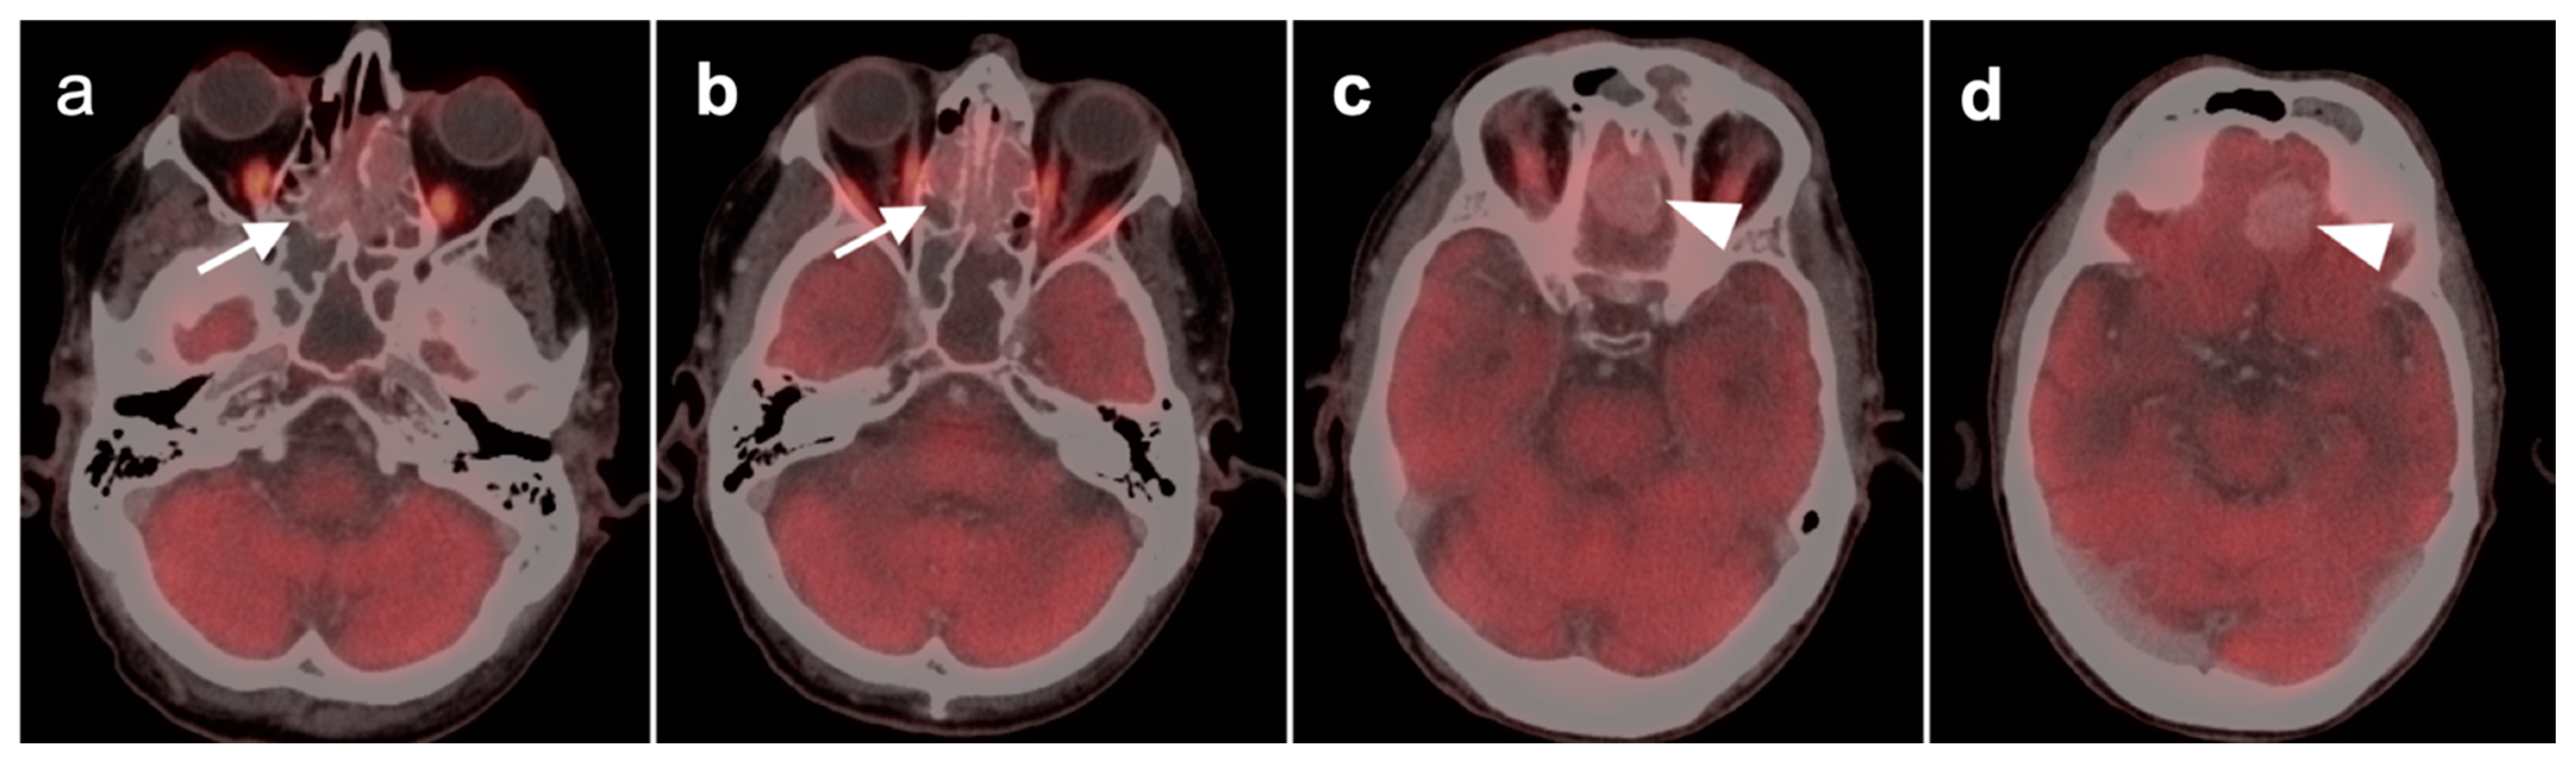

2.4. Sinonasal Tumors

- Sinonasal squamous cell carcinoma

- 2.

- Sinonasal adenocarcinoma

- 3.

- Sinonasal undifferentiated carcinoma

- 4.

- Esthesioneuroblastoma